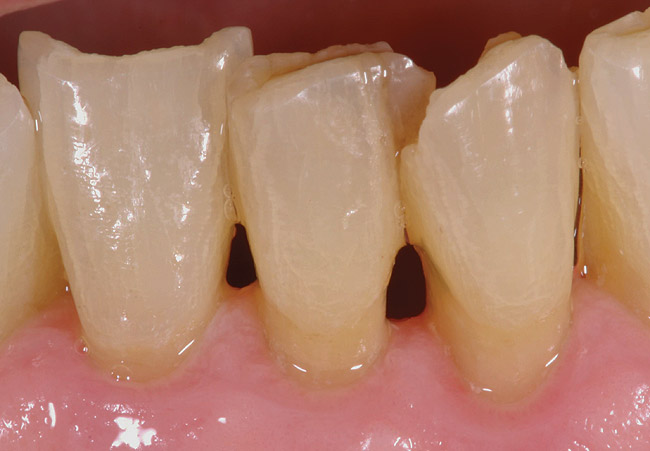

Figure 3  This root surface has a dull surface and is discolored. This indicates the progression of the demineralization/caries process. No cavitation has occurred due to this process. This root surface will feel slightly tacky and softened when exploring with the side of the explorer.

Figure 3